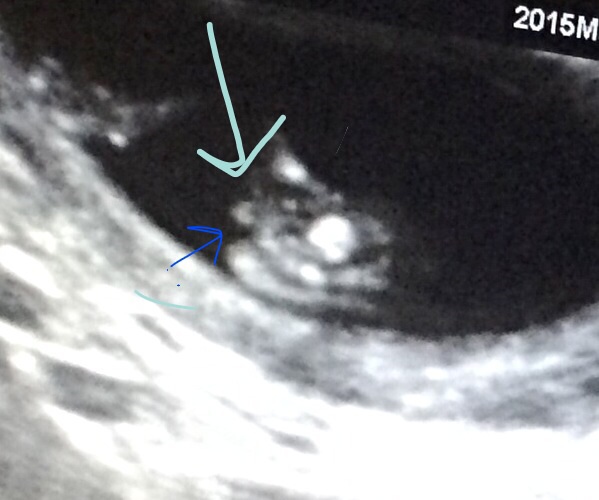

13+6, I go to a super small clinic where the ultrasound machine is like a mini macbook. We also had to take pictures with our phones! Dr. did make a boy guess.

I know it's early but dr. looked for about 15 mins and made a guess. I am not too sure. Other opinions appreciated! Last one is labeled to show how DR was looking at baby. The baby was a wiggler, and a bit on it's side.